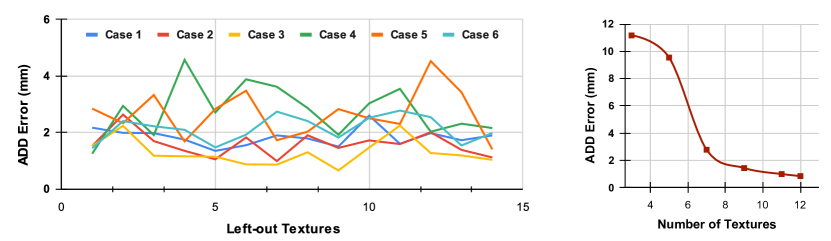

Validation and Evaluation of Texture Invariance

We chose to follow a Leave-one-Texture-out cross-validation strategy to validate our model. This strategy seemed the most adequate to prevent over-fitting on the textures. We measured the ADD errors of our model for each case and report the results in Fig. 4-(left) for each left-out texture. We observed a variance in the ADD error that depends on which texture is left out. This supports the need for varying textures to improve the pose estimation. However, the errors remain low, with a mm average ADD error, over all cases. The average ADD error per case (over all left-out textures) is reported in Tab. 1. We measured the impact of the number of textures on the pose accuracy by progressively adding new textures to the training set, starting from 3 to 12 textures, while leaving 3 textures out for validation. We kept the size of the training set constant to not introduce size biases. Fig. 4-(right) shows that increasing the number and variation of textures improved model performances.